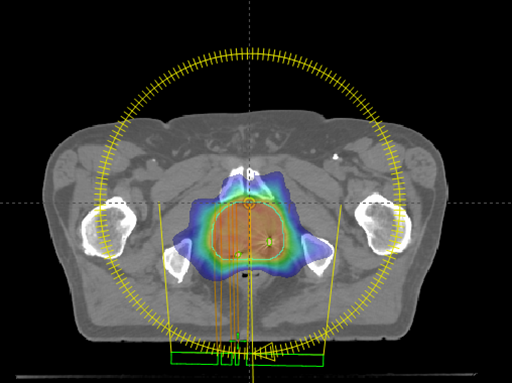

La radiothérapie conformationnelle avec modulation d’intensité (RCMI) et la radiothérapie avec modulation d’intensité Volumétrique par Arc Thérapie (VMAT)

Il s’agit d’une évolution de la radiothérapie conformationnelle tridimensionnelle qui permet non seulement d’adapter la forme du faisceau au volume cible mais aussi de faire varier l’intensité des rayons à l’intérieur du faisceau. Cette technique est particulièrement utile en cas de volume de forme complexe.

L’arcthérapie volumétrique modulée (VMAT) est une forme perfectionnée de RCMI, durant laquelle la dose de rayon est délivrée au cours d’une rotation continue allant jusqu’à 360° de l’appareil de traitement. Le traitement est plus rapide qu’en RCMI.

Dosimétrie

Durant cette étape, le dosimétriste va réaliser un plan de traitement sur un logiciel pour délivrer la dose prescrite à la tumeur tout en protégeant au maximum les tissus sains avoisinants. Ce traitement sera alors validé par votre médecin et un physicien médical.